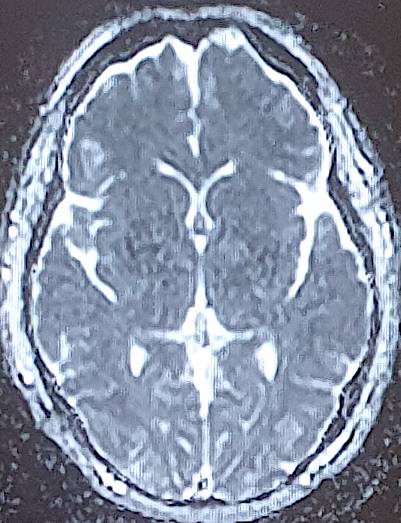

The average consultation time was 24.3 ± 14.4 hours, with extremes of 7 hours and 44 hours. Clinical presentations were headache (88.2%), visual disturbance (64.7%), disturbed consciousness (35.3%), epileptic seizures (23.5%) and motor deficit (29.4%) (Table 2). Mean systolic blood pressure was 190 ± 5.7 mmHg (extremes 150 - 24 mmHg), mean diastolic blood pressure 110 ± 5.1 mmHg (extremes 80 - 160 mmHg). Neuroradiological lesions (Figure 1) were edematous (88.2%), hemorrhagic (23.5%) and ischemic (11.7%). The topography of cerebral lesions was occipital (100%), parietal (82.3%), frontal (58.8%), temporal (47%), cerebellar (29.4%) and basal ganglia (23.5%) (Table 3).

Figure 1. Breakdown of cases by neuroradiological lesions.

Our findings on lesion topography (Figure 2 and Figure 3) are similar to those in the literature, which report that the parieto-occipital, frontal and temporal regions are most involved. More rarely, lesions may extend to the basal ganglia (14%), brain stem (13%) and splenium of the corpus callosum (10%) (Leroux et al., 2008). A normal CT scan does not exclude the diagnosis of PRES (Poma et al., 2014). Intracerebral hemorrhage is observed in 5% - 30% of PRES cases (Aracki-Trenkić et al., 2016; McKinney et al., 2012).

Figure 2. Bilateral occipital vasogenic edema.

Figure 3. Bilateral frontal-parietal-occipital edema with left lenticular hemorrhage.